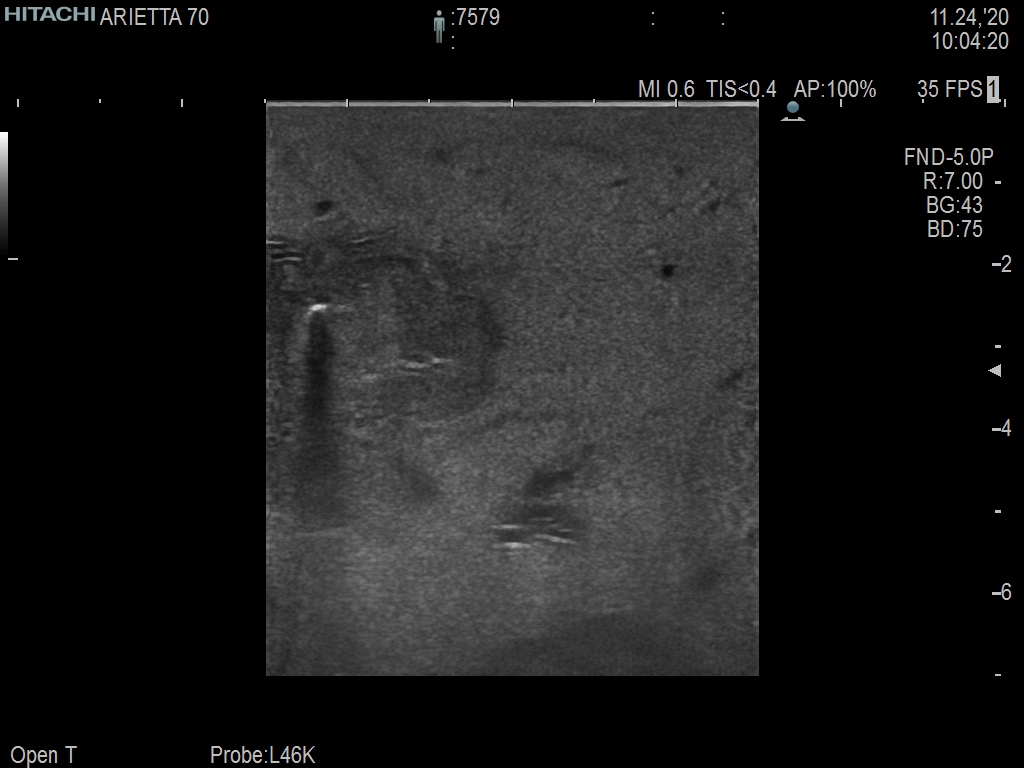

Arietta 70

Recognized for our outstanding image quality, outstanding system reliability and intuitive use of cutting edge technology, Fujifilm Healthcare remains the standard in the field of Surgery.

Learn moreArietta 70

Recognized for our outstanding image quality, outstanding system reliability and intuitive use of cutting edge technology, Fujifilm Healthcare remains the standard in the field of Surgery.

The Fujifilm Healthcare transducer utilizes the full benefits of the Wrist Articulation™ of the robotic instruments to capture real-time ultrasound imaging even at complex angles and difficult-to-reach areas.

A critical function of robotic ultrasound guidance is tumor margin identification. Fujifilm's family of robotic probes all have the optimum location of the attaching mechanism that allows for full wrist articulation of the probe. The result is an increased confidence that the tumor margins have been completely identified.